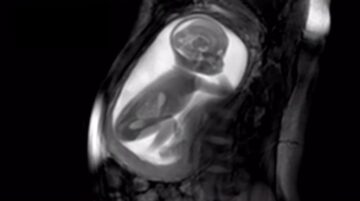

El material que consiguen es tan detallado que se puede ver al bebé girando el cuello, jugando con el cordón, saltando, encongiéndose, etc. En el caso del vídeo, el feto tiene 20 semanas de vida y por eso se le ve el cuerpo entero.

Y esto es lo más increíble: mediante unos algoritmos, el ecógrafo es capaz de captar la imagen de todo el útero e incluso el cuerpo de la madre, en alta calidad. Nada de ver un brazo, ahora una pierna, ahora la cabeza, ahora «no sé qué es esto», etc. En una sola imagen se ve al bebé por completo, de manera que se puede tener una idea muy clara de lo que está haciendo en cada momento.

Gracias al método de captación de imágenes, no sólo puede verse el exterior del bebé, sino también el interior, con gran definición. De este modo, incluso los bebés que se mueven mucho en el útero pueden ser grabados para analizar después las imágenes con detenimiento, y valorar si todo se está desarrollando con normalidad.